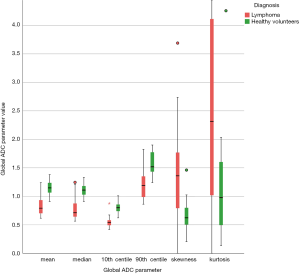

Table 2 shows the performance of the significant gADC discriminators. The order of the diagnostic accuracies of gADC parameters by AUC performance from highest to lowest was: 10th centile, mean, median, 90th centile, skewness and kurtosis. Figure 2 visualises the overlap of gADC parameters between lymphoma and healthy individuals. There was no significant difference of AUC between mean and median gADC, 10th and 90th centile gADC (each P>0.131). Mean gADC AUC was significantly larger than gADC skewness AUC (P=0.032) and gADC kurtosis (P=0.004). 10th centile and median gADC AUC were significantly larger than for gADC kurtosis (each P<0.010). Median and 90th centile gADC AUC were significantly larger than for gADC skewness (each P<0.043). In correspondence to the AUC, the highest Youden index among gADC histogram parameters was calculated for the 10th centile gADC at a threshold of 0.67×10−3 mm2/s, smaller values identifying disease with 91% sensitivity and 95% specificity. A median gADC value less than 0.91×10−3 mm2/s identified disease with 87% sensitivity and 95% specificity. 81% sensitivity and 95% specificity was shown for a threshold mean ADC value of 0.95×10−3 mm2/s. Sensitivity of the 10th centile cut-off was significantly larger than for the mean gADC cut-off (P=0.046). Exemplar maximum intensity projections delineating lymph nodes of a lymphoma patient and a healthy volunteer are demonstrated in Figure 3. Figure 4 visualises the corresponding gADC histograms of lymphoma and healthy nodes of this particular patient (A) as well as the ADC distribution across all study subjects in both groups (B). No gADC parameter showed significant difference between different lymphoma subtypes (each P>0.324).